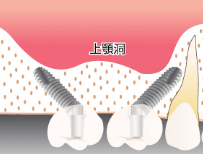

先ほどもお伝えしましたが、CTとは、立体的 (三次元) に骨の状態や神経の位置を把握できる特殊な撮影装置です。

二次元のレントゲン (歯科医院にある通常のレントゲン) では見えなかった事、分からなかった事が、歯科用CTなら明らかにすることができ、それが正確な診査と診断へとつながり、安全性と治療のクオリティーを高めることが可能となりました。

医療において「見える」「見えない」は治療クオリティーに大きな差が出ます。

ましてや外科手術を伴うインプラントにおいてはなおさらです。

これまでのインプラント事故は、ドクターの未熟さが大きな原因を占めますが、CT撮影を行わず、あいまいな状態で (二次元レントゲンのみの診断) オペを遂行したことにより生じてしまった事故もあります。

インプラント手術においてCT撮影は必須です。

骨の厚さや神経、血管の位置などですね。

どの部分に、どの方向に、どのくらいの深さまで、どのサイズのインプラントを埋入するだとか、ここには神経、血管が走っているので避けてインプラントを埋入しようなどです。